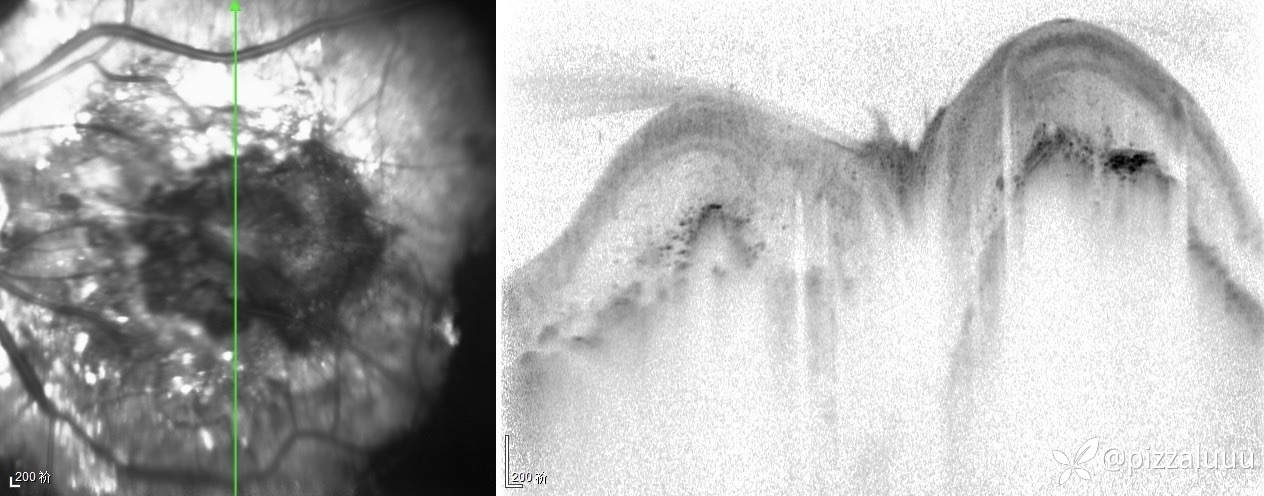

左眼轻度外斜,各位老师考虑这是什么病变?今天只做了这两项检查

玻璃体清,后极部球壁局限隆起,表面粗糙,其内回声不均